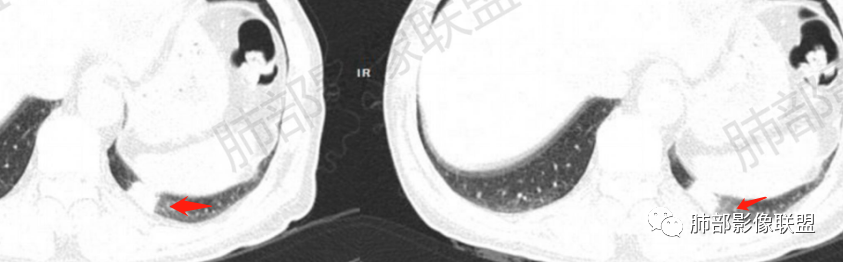

晨读:左肺下叶胸膜下实性结节影边缘毛糙,有毛刺,分叶,近段支气管未见显示,可能堵塞,远端宽基底与胸膜相贴,边缘平直,部分彭隆,病灶局限、单发,无增强,不好判断肿瘤血供,临床男性,63岁,无症状,体检发现,有吸烟史,考虑恶性:腺癌,鳞癌,小细胞肺癌,鉴别:肺隐球菌建议增强及穿刺检查。

晨读病例,老年人 ,吸烟史,左肺下叶结节影,密度均匀,边缘毛糙,周围可见长毛刺,病灶边缘分叶,局部膨隆,部分边界平直,收缩,病灶相邻胸膜处可见糊墙征象,病灶近肺门处见支气管堵塞,考虑恶性病变,周围型肺癌:鳞癌伴肺不张>腺癌,鉴别隐球,炎性假瘤。

细、长、软毛刺

边缘模糊,支气管关系不明确

糊墙,胸膜下脂肪间隙明显增厚

边缘平直为主,部分膨隆,糊墙征

密度比较均匀;